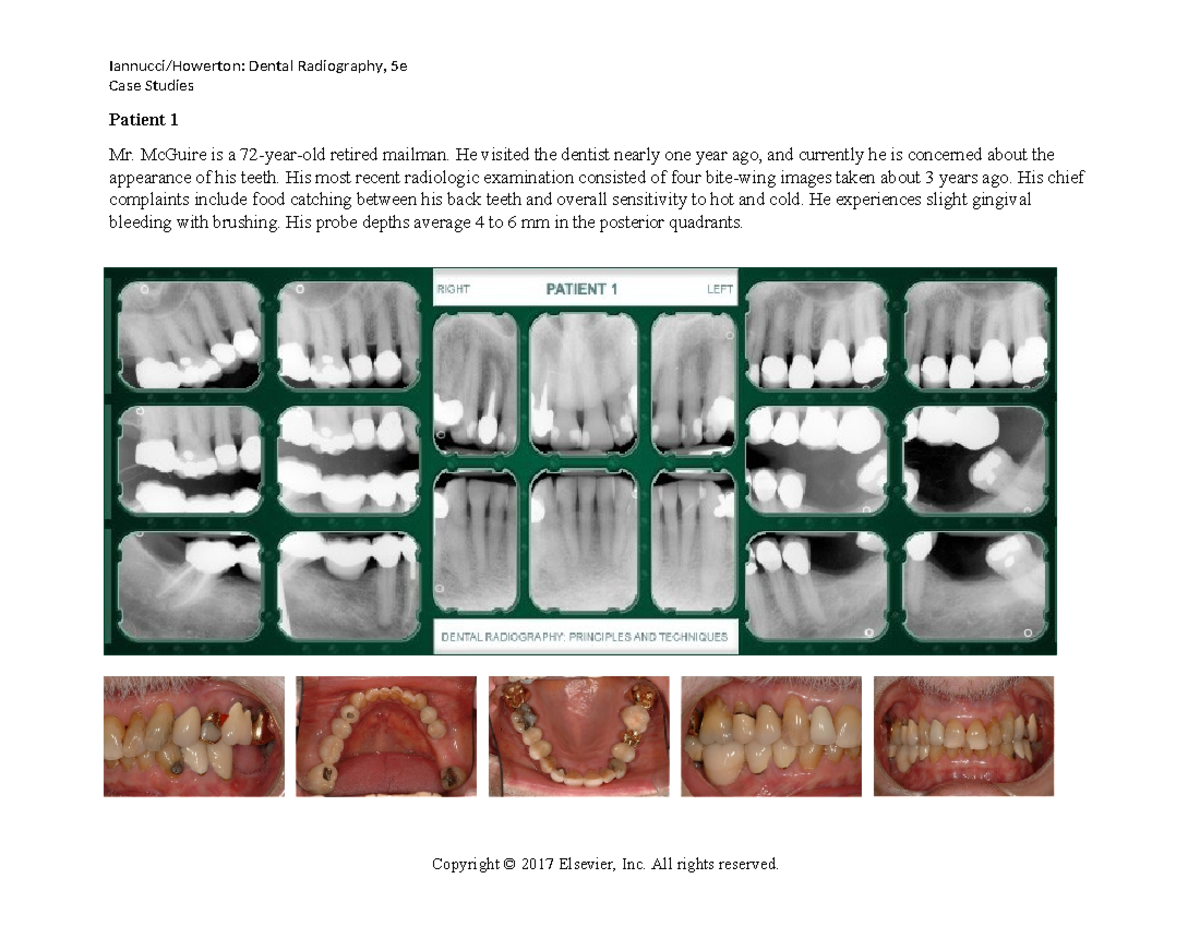

Patient 1 Questions and Images Iannucci/Howerton Dental Radiography Dental Radiography Iannucci Iannucci and laura jansen howerton, elsevier’s bestselling text on dental radiography prepares you for success in the. Iannucci and laura jansen howerton, elsevier's bestselling text on. written by noted educators joen m. written by noted educators joen m. written by noted educators joen m. written by noted educators joen m. Iannucci and laura jansen howerton, elsevier’s. Dental Radiography Iannucci.